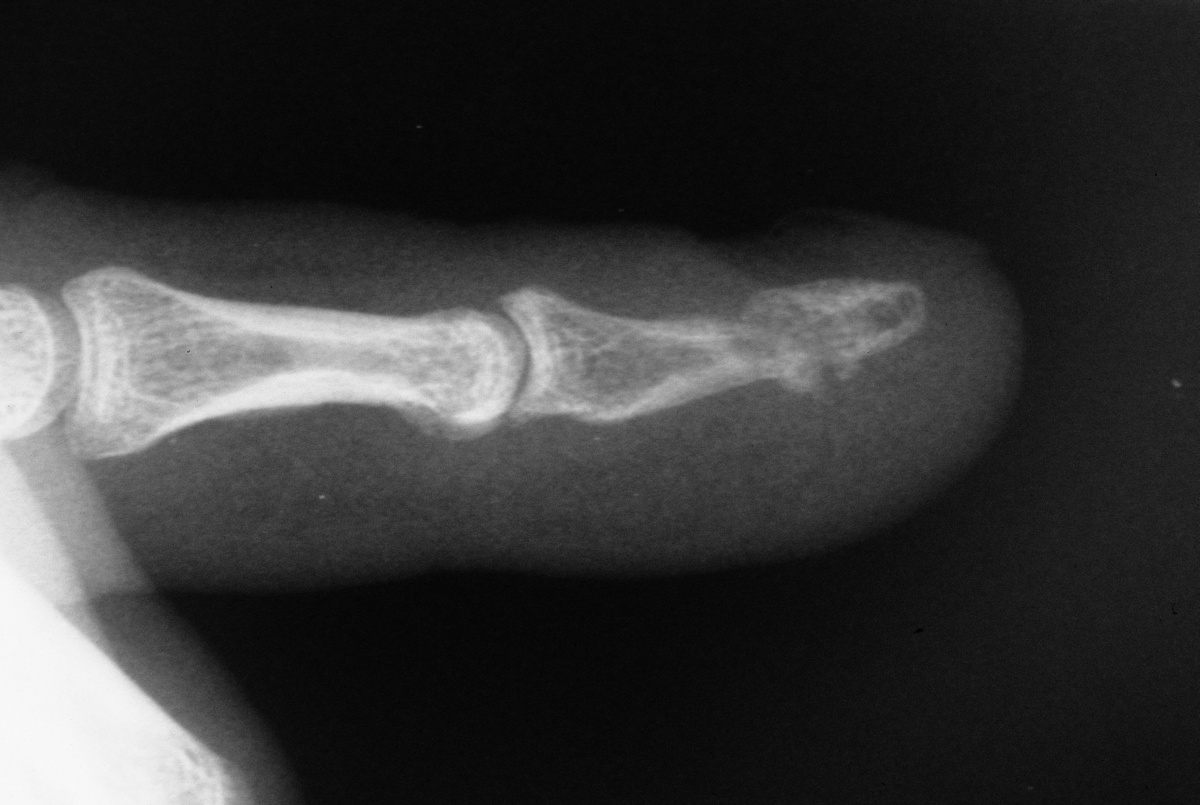

| The distal nail

plate fragment was removed, and the fracture was

stabilized with K-wires as in case 1. |

| Two months

following hardware removal. |